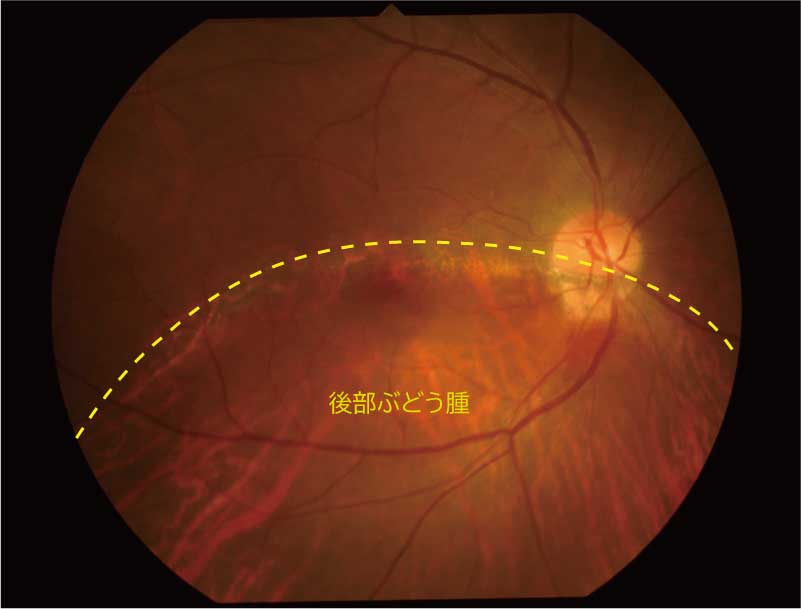

59歳 女性

視力 右眼 0.06(1.0p×-3.25=c-2.50A150°)

左眼 0.03(0.2×-3.75=c-1.00A35°)

主訴 左眼の視力低下で受診。

乳頭が下鼻側に傾斜し、下方に萎縮(PPA)がみられる。

両眼ともに、後部ぶどう腫staphylomaの上縁に一致して乳頭下縁から黄斑を横断するように帯状の網脈絡膜の萎縮巣がみられる。また後部ぶどう腫領域に一致して網膜・脈絡膜が菲薄化しているため、紋理眼底tessel lated fundusがみられる。

後部ぶどう腫の上縁に漿液性網膜剥離(SRD)がみられる。この後部ぶどう腫と正常部の境界付近に脈絡膜新生血管の発生を見ることもあるため、注意が必要。